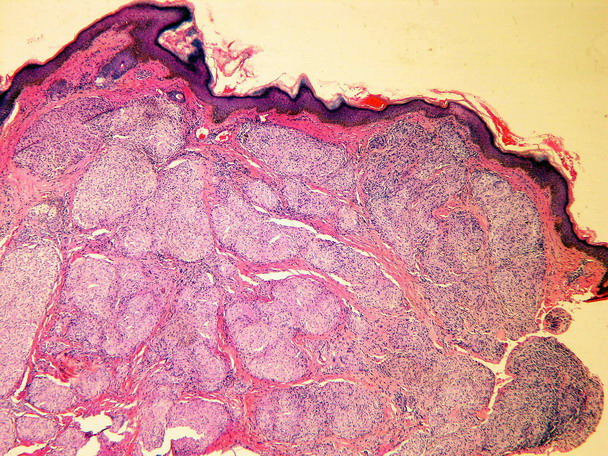

Histology[edit | edit source]

Sharply demarcated circular non-caseifying granulomas. Composed of epithelioid macrophages (histiocytes), surrounded by a negligible lymphocyte infiltrate. They are therefore referred to as "naked".